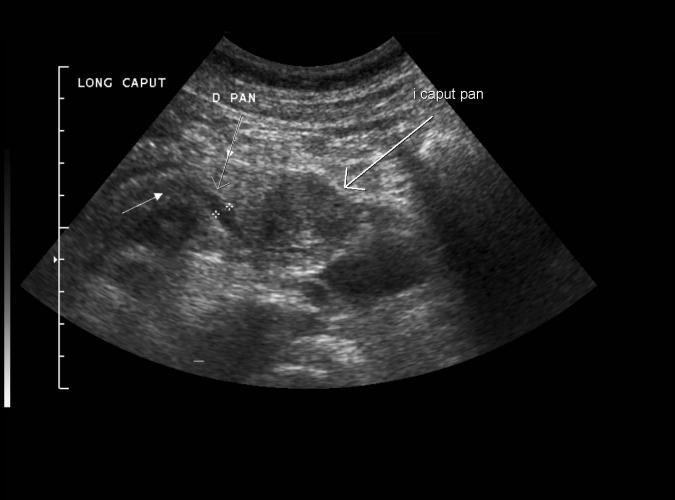

Samma patient som i 29a. Long. lågekogen tumör i caput pancreas i en 48årig. Whipple op.adenocarcinom ..se long. bild 6a.